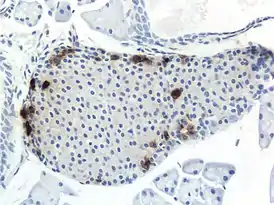

![]() Панкреатический островок мыши, ПП-клетки выделены. | |